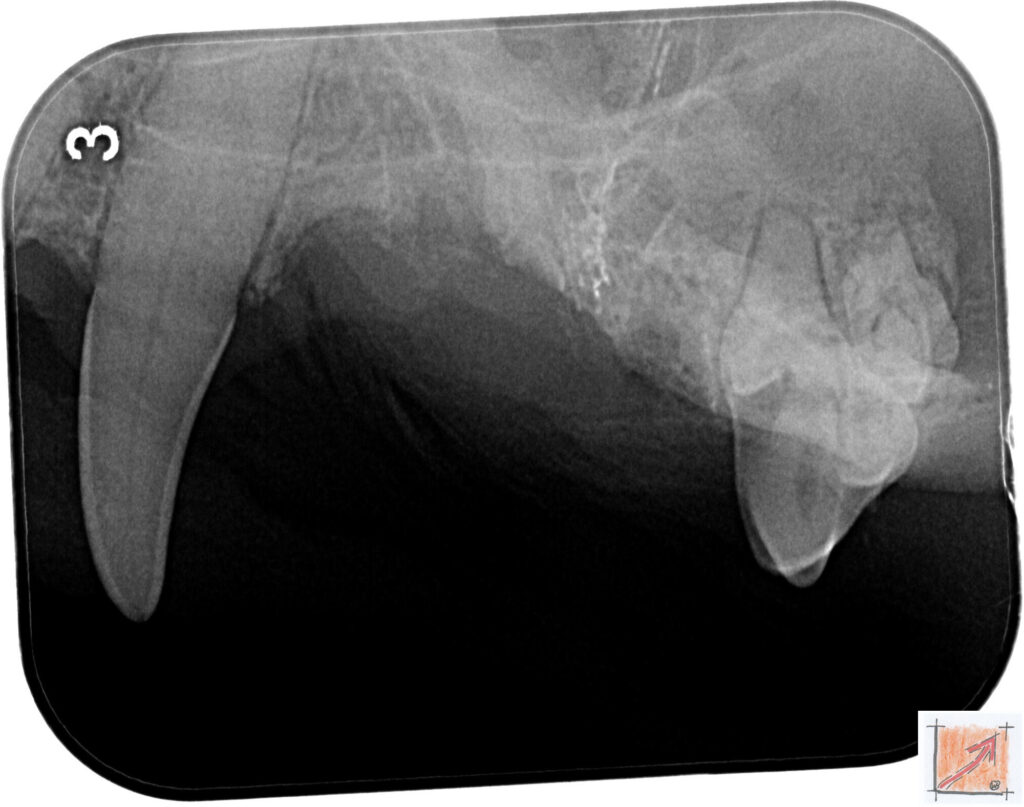

Röntgenbilder vom Thierrischen Orakel bei der Zahn-OP:

Warum Dentalröntgen beim Chihuahua lebenswichtig ist:

Ein Blick hinter die Kulissen von Chihuahua-Zähnen:

In dieser Galerie zeigen wir exklusive intraorale Röntgenaufnahmen einer Zahn-Operation beim Thierrischen Orakel als Chihuahua vom BauFachForum. Während oberflächlicher Zahnstein oft sichtbar ist, verbirgt sich die wahre Gefahr für das Herz meist unter dem Zahnfleischsaum.

Das digitale Dentalröntgen ist der Goldstandard in der modernen Tiermedizin, um parodontale Entzündungsherde und Wurzelabszesse sicher zu diagnostizieren. Für Chihuahuas wie dem Thierrischen Orakel, mit Mitralklappeninsuffizienz ist dieser diagnostische Schritt essenziell. Nur wenn versteckte Bakterienherde an der Zahnwurzel oder mit dem Fachbegriff Apikalabszesse erkannt und saniert werden, kann das Risiko einer bakteriellen Endokarditis oder einfach ausgedrückt einer Herzinnenhautentzündung minimiert werden.

Unsere Aufnahmen von Patienten dem Thierrischen Orakel verdeutlichen den Unterschied zwischen einer rein optischen Zahnreinigung und einer medizinisch fundierten Sanierung unter Röntgenkontrolle.

Chihuahua Mitralklappeninsuffizienz Trachealkollaps:

Wichtig ist im Vorfeld die Zahnhygiene des Chihuahuas. Die Bilder zeigen Dentale Röntgenbilder vom Thierrischen Orakel als Chihuahua-Hund während seiner Zahn-OP. Darstellung von Kieferknochen und Zahnwurzeln zur Diagnose von Parodontitis.

Zahnröntgenaufnahme bei Chihuahua Thierry:

Untersuchung der Zahnwurzeln auf Entzündungsherde als Prophylaxe gegen bakterielle Endokarditis.

Intraorales Dentalröntgen eines Chihuahuas:

Die Bilder zeigen Zähne und Wurzelstrukturen im Unterkiefer zur Planung einer Extraktion bei hochgradigem Zahnstein.